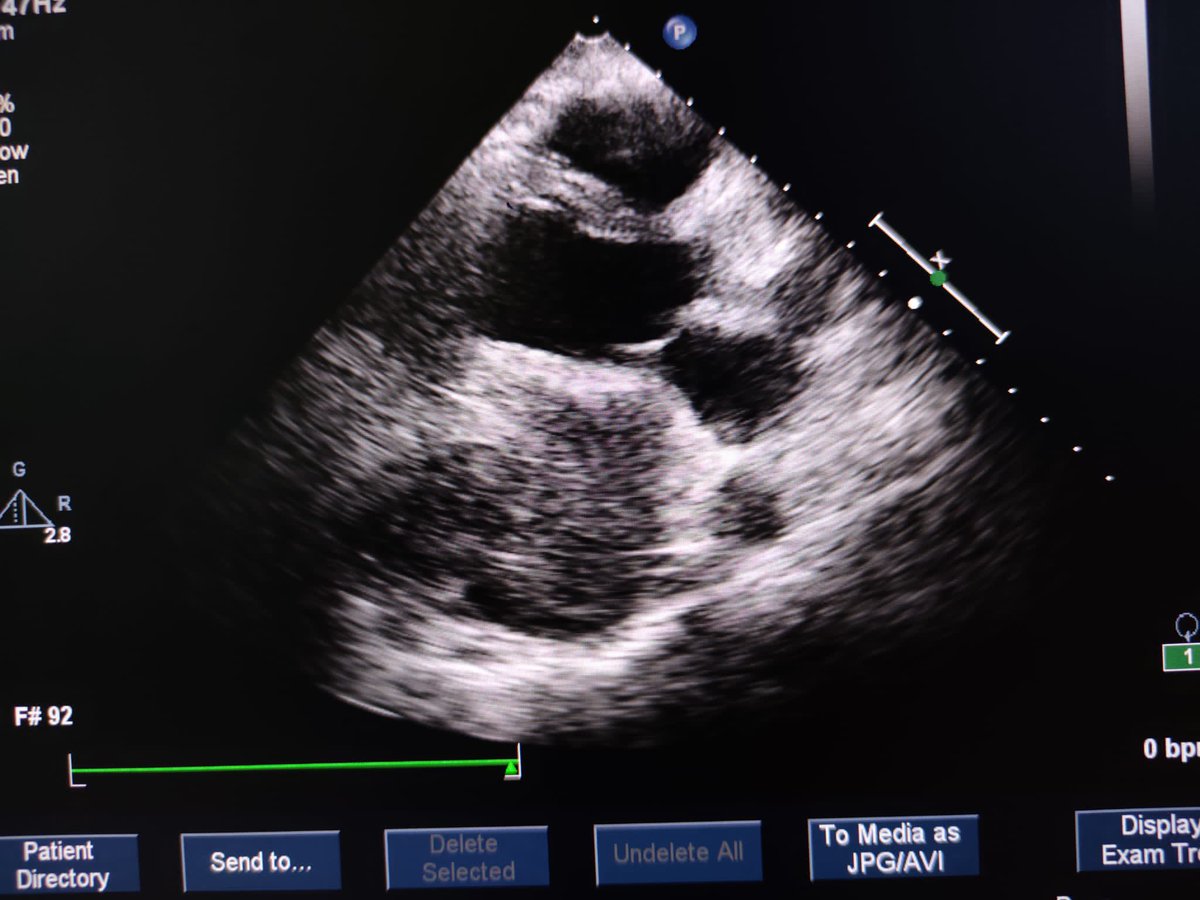

Our editorial @ASE journal. LA strain reservoir strain(LARS) is a sensitive marker of LA dysfunction. LVGLS and LARS are associated with hemodynamic severity of MAC, and are independent predictors of CV outcomes in MAC.bit.ly/47IB9u0 @iamritu @DocStrom @OchsnerCardio @pattypellikka